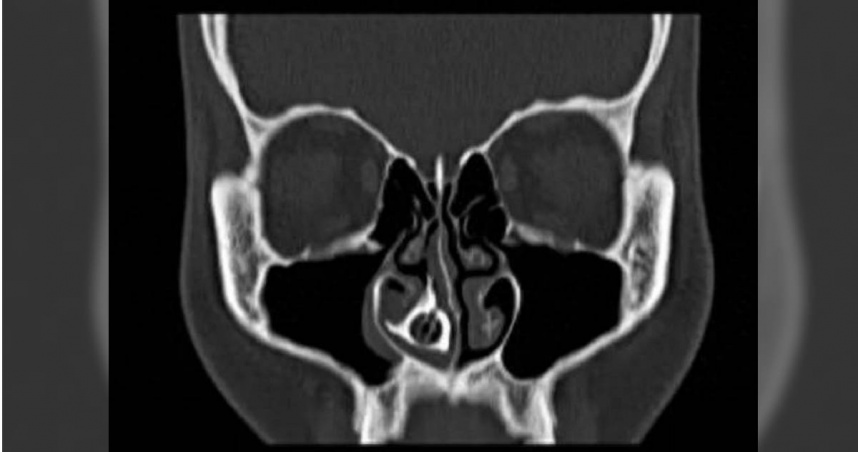

隨後經過電腦斷層(CT)檢查證實,一個邊界清晰的球狀物體已在阿花鼻腔內「安家落戶」多年,由於異物滯留時間過久,已與周邊組織嚴重嵌頓,並形成堅硬的鼻石。最終院方安排全麻手術,醫療團隊先將阿花鼻腔內的結石擊碎後才分塊取出,剝離結石後,確認該異物是一顆紅色的中空圓形串珠,推測為手鍊上的飾品。